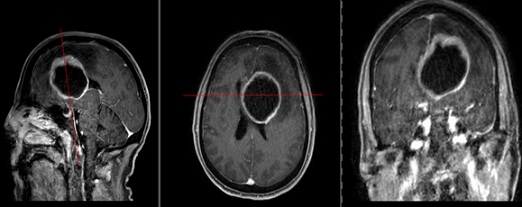

A 59-year-old female with LCNEC presented with progressive neurological symptoms, leading to a comprehensive re-evaluation. Initially, an intracranial cystic-necrotic metastasis in the left frontal lobe was identified (Figure 1), correlating with new-onset aphasia and confusion. Post-surgical analysis confirmed high-proliferation LCNEC, positive for synaptophysin, chromogranin A, CD56, and RB1 wild type. Primary lung involvement was evident in the right upper lobe. Despite cisplatin and etoposide-based radio-chemotherapy, extensive neurocranial and leptomeningeal carcinomatosis (LMC) developed (Figure 2). Whole-brain irradiation (10 x 3Gy) was administered as palliation. By October 2023, the patient experienced right dominant paraparesis, saddle hypesthesia, urinary incontinence, and weakened sphincter function. MRI revealed extensive intradural LMC, compressing the cauda equina at the L4/L5 level (Figure 3). Emergency radiotherapy (Th12-S1, 10 x 3Gy) was initiated, with extended coverage to C1-Th11. Initial improvement was noted; however, the patient's condition progressed to paraplegia.

Figure 2: T1-weighted MRI of the skull with contrast agent (sagittal, axial, and coronal views). There is a pre-existing resection cavity in the left frontal lobe. Multiple intracerebral metastases are noted, including in the left frontal medial gyrus, left parietal gyrus, left precuneus, and left temporal gyrus. Increased dural enhancement is observed in the left parietal and frontal regions, indicative of leptomeningeal carcinomatosis.